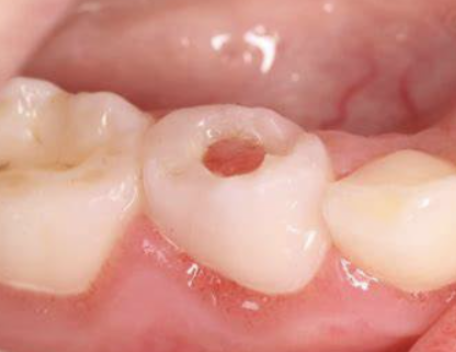

Wat is cariës profunda?

Cariës tot in de pulpa.